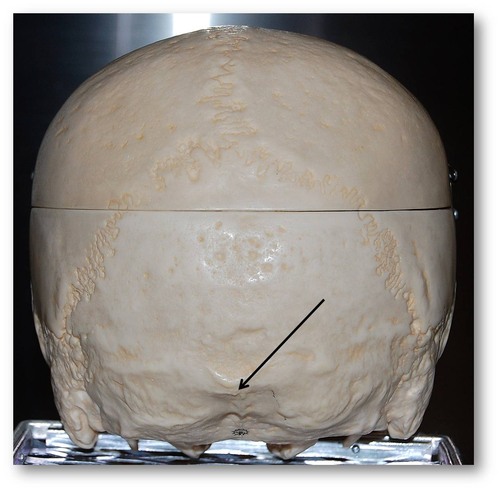

occipital condyle

foramen magnum

occipital bone